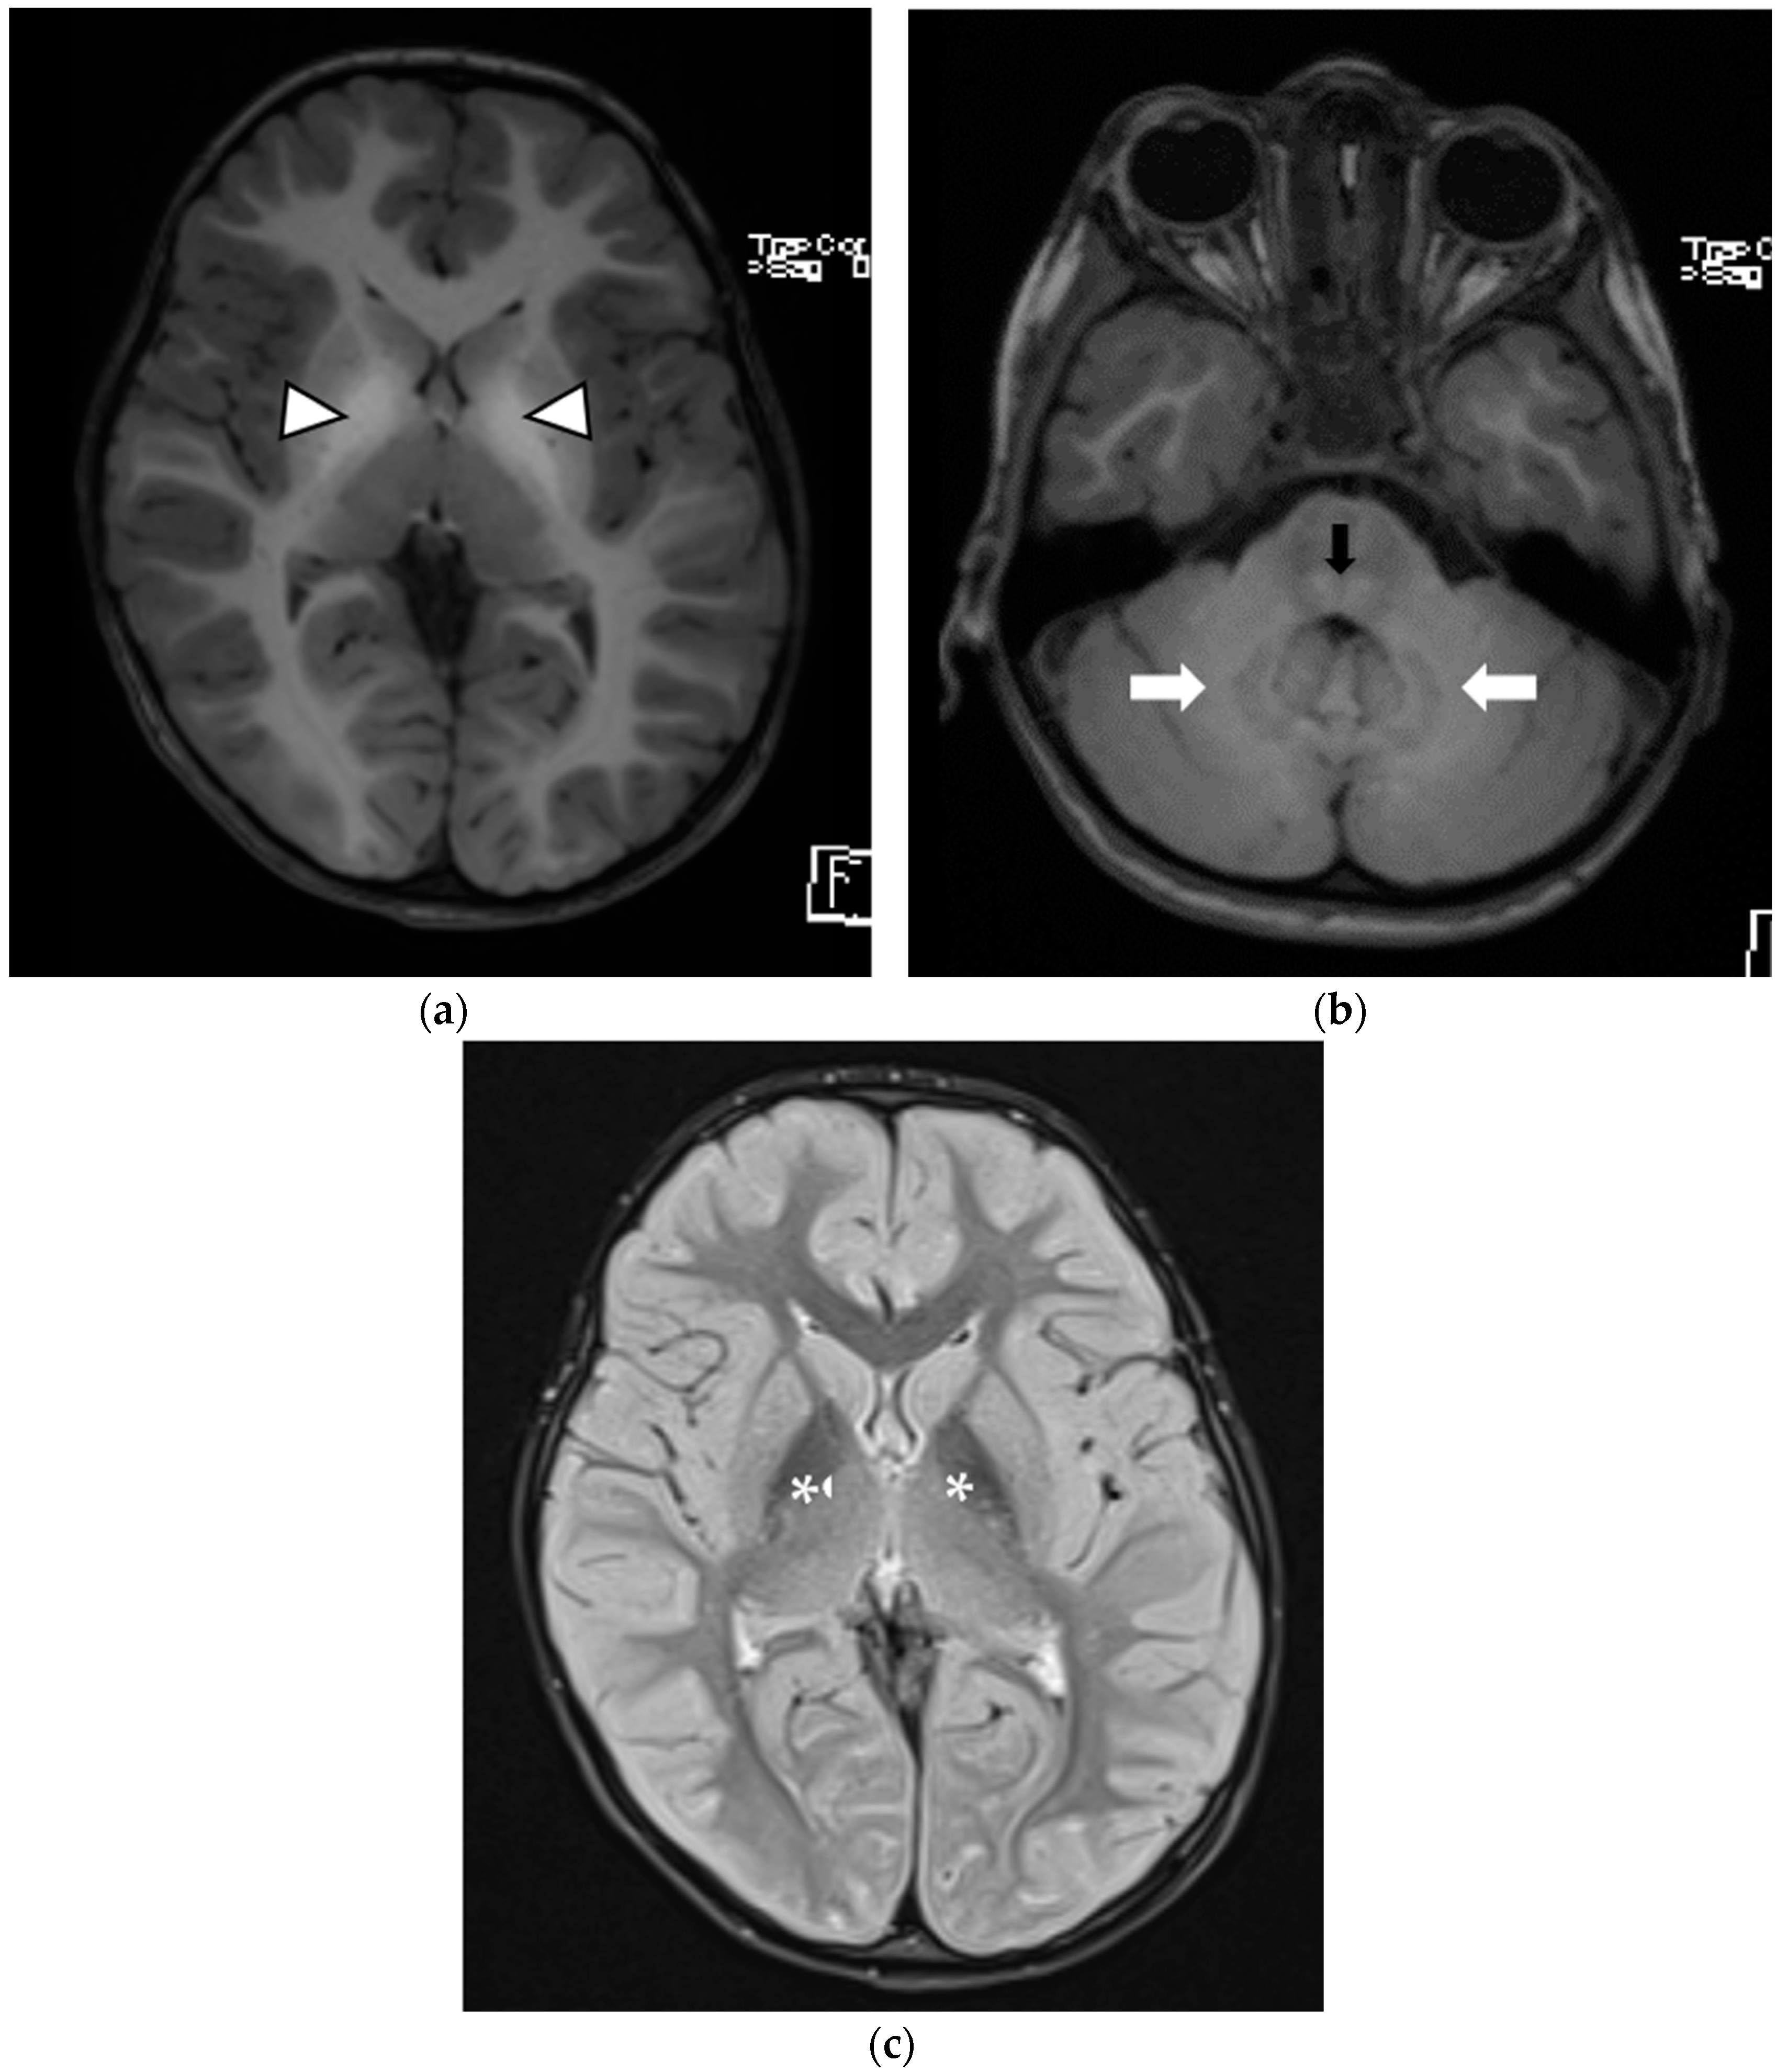

| Brain MRI findings at the time of diagnosis | Symmetrical involvement of the basal ganglia, with decreased T2 and increased T1 signal intensity Mild global atrophy Mildly enlarged eye globes | Symmetrical involvement of the basal ganglia, with decreased T2 and increased T1 signal intensity, and the involvement of cerebellar white matter and posterior brain stem to a lesser degree | Symmetrical involvement of the basal ganglia, tegmentum of the midbrain, posterior tegmentum of the pons, both superior cerebellar peduncles and dentate nuclei, with decreased T2 and increased T1 signal intensity |

| Follow-up brain MRI | Not performed | Similar changes to those observed at initial MRI, with no new lesions and no extension of previous lesions | Similar changes to those observed at initial MRI, with no new lesions and no extension of previous lesions |